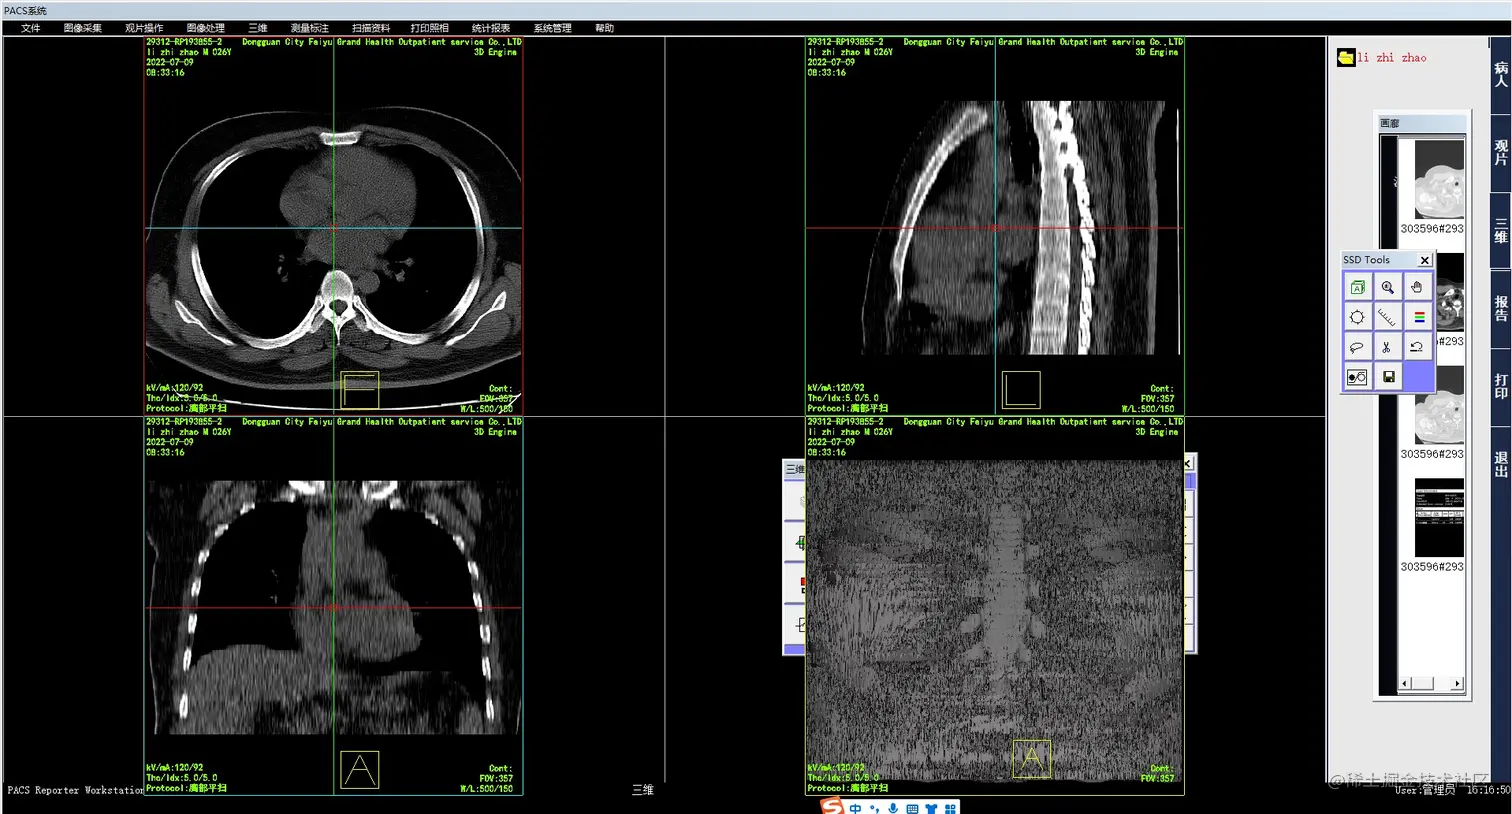

1、MPR    MPR(Multi-Planar Reformatting),多平面重建,是将扫描范围内所有的轴位图像叠加起来再对某些标线标定的重组线所指定的组织进行冠状、矢状位、任意角度斜位图像重组。MPR适用于任一平面的结构成像,以任意角度观察正常组织器官或病变,可以显示腔性结构的横截面以观察腔隙的狭窄程度、评价血管受侵情况、真实地反映器官间的位置关系等。

优点: a. 能任意产生新的断层图像,而无需重复扫描 b. 原图像的密度 值被忠实保持到了结果图像上 c. 曲面重组能在一幅图像里展开显示弯曲物体的全长。

缺点: a. 难以表达复杂的空间结构 b. 曲面重组易造成假阳性。